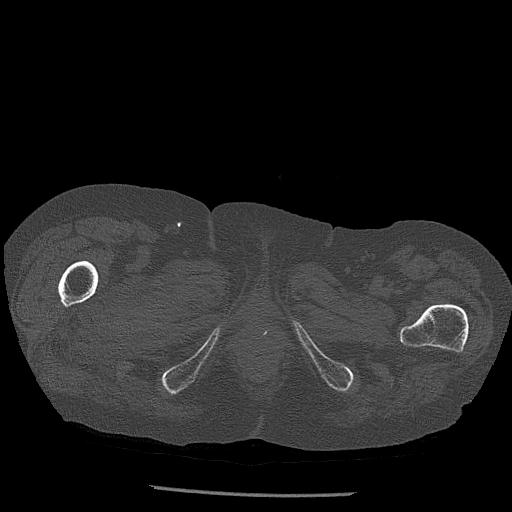

100703 1/27 両股正面+軸 1/29 両股正面+軸 94歳女性 パンソンロン

46666 1/28 両股正面+軸と 1/26 右手関節 2R 76歳女性 右転子部骨折

37 1/18 両股正面+軸 1/22 2R 86歳女性 右転子下